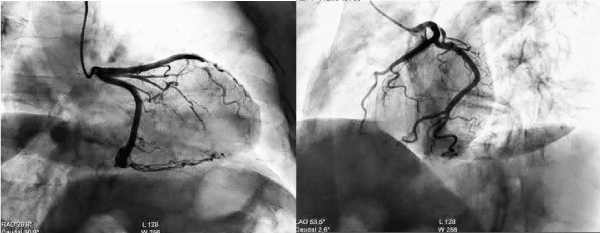

A 58-year-old female, with no prior medical history, presented to the ED for sudden nocturnal sharp chest pain radiated to the back. Her first ECG resulted quite normal (Figure 1), while blood analysis found out specific highly sensitive Troponin over normal limits (82 ng/L first check, then 400). Additionally, a fast echocardiogram showed marked hypokinesia at the mid-apical segment of left ventricular septal wall. She was immediately treated for Acute Coronary Syndrome (ACS) with beta-blocker, venitrin infusion, antiaggregant and anticoagulation therapy with pain relief and stable hemodynamics. Then, the patient was taken urgently to the catheterization lab where she was found to have to have a right hypoplastic coronary artery and a dominant left coronary artery free of atherosclerotic obstructive disease (Figure 2). The ECG of the day after (Figure 3), taken during the recovery in the cardiology department, showed significant changes in the ST-segment and T-wave in the precordial anteroseptal leads which suggested ischemia. Anyway, a few days later she was discharged in good health from the hospital with a diagnosis of suspected myocarditis. A follow-up ECG done at the GP's office (Figure 3) showed that the significant changes recorded in the cardiology department were more accentuated, confirming ST-segment elevation and Negative T-waves in the precordial anteroseptal leads. Also, a TTE confirmed a slight anteroseptal hypokinesis. Subsequently, 15 days later a CMR was performed to rule out myocarditis or other pathologies with myocardial damage, as both cardiologists and GP's have suspected. However, radiologists reported that no signs of myocarditis were shown by the CMR and there was no mention of myocardial damage like oedema or scar or signs of microvascular obstruction (MVO), even though some images (Figure 4) could suggest oedema on the Antero-mid-septal and apical wall suitable for microvascular obstruction compatible with the ECG findings and clinical presentation.

Figure 2. Coronary angiography with NON-obstructive CAD.